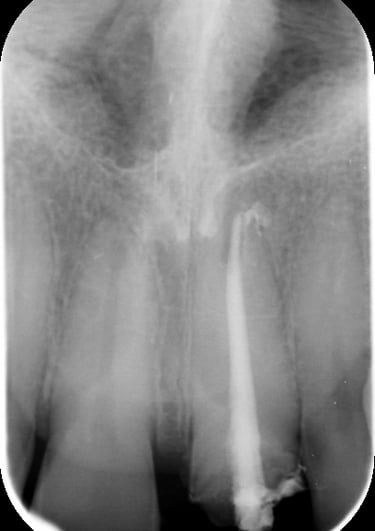

Trattamento Canalare Incongruo

1. Ritrattamento Endodontico

Il primo step è stato il ritrattamento endodontico, essenziale per garantire la salute a lungo termine del dente. Dopo la rimozione della vecchia otturazione canalare, è stata effettuata una detersione accurata con irriganti specifici e successiva otturazione tridimensionale per prevenire recidive infettive.

Trattamento Canalare Congruo